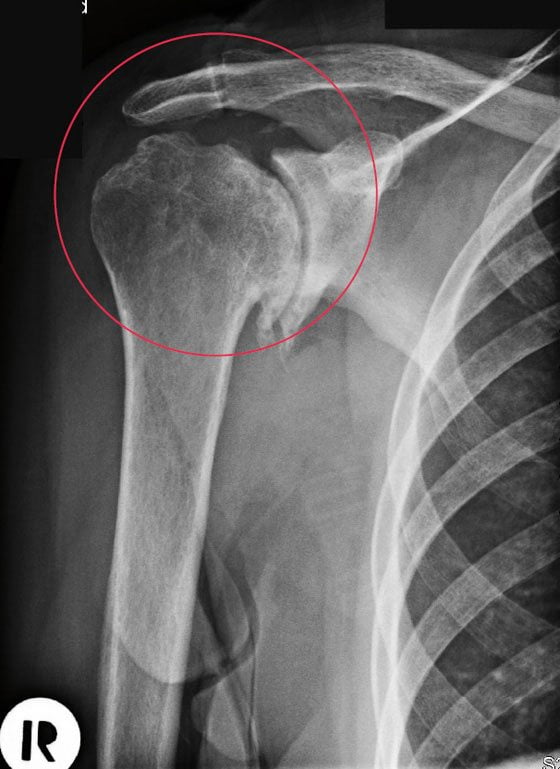

Деформирующий артроз плечевого сустава 1 степени на рентгенограмме практически незаметен. Иногда удается установить небольшое сужение суставной щели. Однако при более серьезном обследовании – КТ или МРТ, поражение костно-хрящевой структуры четко заметно. Видны начальные деформации суставных поверхностей, отек подлежащих мягких тканей, небольшая узурация.

Деформирующий артроз плечевого сустава 2 степени проявляется уже значительными изменениями. Их можно представить так:

- резкое сужение суставной щели;

- деструкция суставных поверхностей;

- краевые остеофиты – костные разрастания;

- дефицит хрящевой прослойки;

- грубая узурация костных структур;

- остеопорозные изменения плечевой кости.

ДОА плечевого сустава 2 степени уже необратим, поэтому нужно стремиться к установлению диагноза именно на 1 стадии.